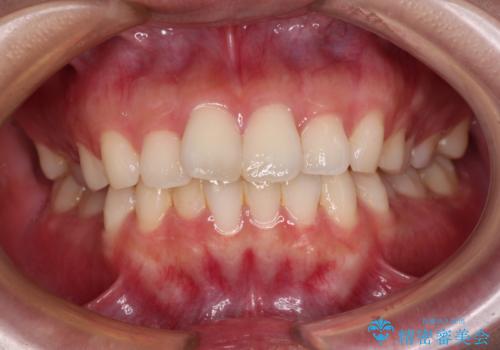

矯正歯科治療 → 上下顎前突(口ゴボ)

- 口元の突出感を改善したい。審美装置による抜歯矯正- 担当医 齋藤佑磨